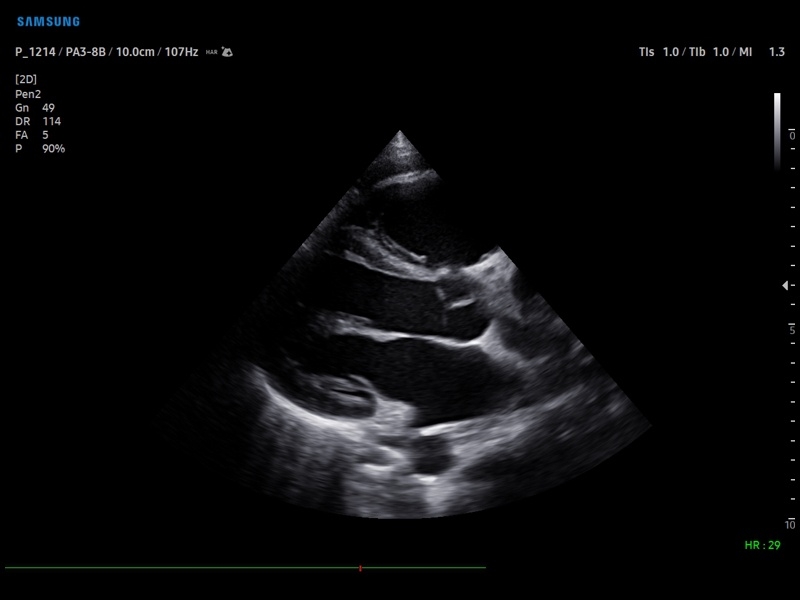

• Кардиологический пакет с функцией StressEcho

• Кардиология

• M - одномерный режим для исследования сердца, анатомический М-режим (необходим кардиопакет), CM - цветной М-режим (необходим кардиопакет).

• Кардиопакет: тканевый допплер (TDI) + анатомический М-режим + цветной М-режим (CM) + программное обеспечение.

• Модуль Stress Echo – программа для исследования сердца под нагрузкой.

• Пакет кардиологических исследований.

М-режим:измерение диаметра аорты, передне-заднего размера ЛП, толщины МЖП (систолическая и диастолическая), толщины ЗСЛЖ (систолическая и диастолическая), размеров ЛЖ и ПЖ (систолический и диастолический), ФВ (Teichholz).

B-режим:измерение диаметра аорты (восходящей, дуги, нисходящей, на уровне синусов Вальсальвы, на уровне створок аортального клапана), определение размеров ЛП и ПП (максимальный, минимальный, систолический, диастолический, переднее-задний, верхнее-нижний, медиально-латеральный), расчет объемов ЛП и ПП, объемов ЛЖ (метод "Площадь-Длина", метод дисков (Simpson)), массы миокарда ЛЖ, индекса массы миокарда ЛЖ.